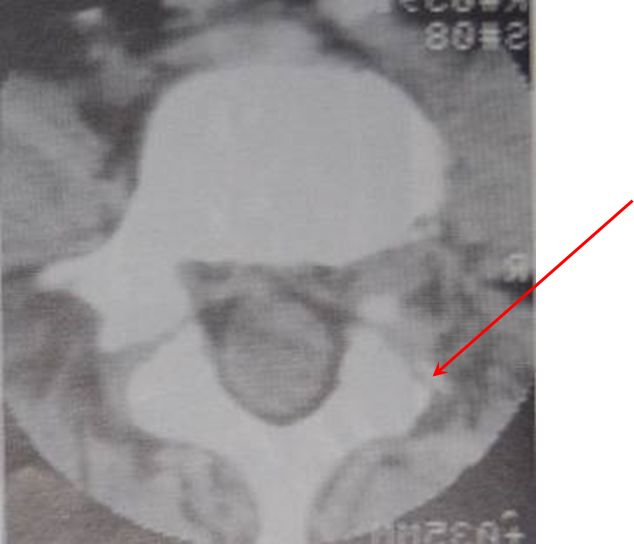

CT扫描

椎弓根下层面可见2~9cm锯齿样裂隙,宽窄不一,走行不定,扫描倾斜时与椎间盘层面正常光滑关节面呈双关节面。

椎管前后径延长,可呈“双管征”。

滑脱椎体“双边征”

椎间盘于相邻椎体层面以相反方向超出椎体边缘“夹心征”。